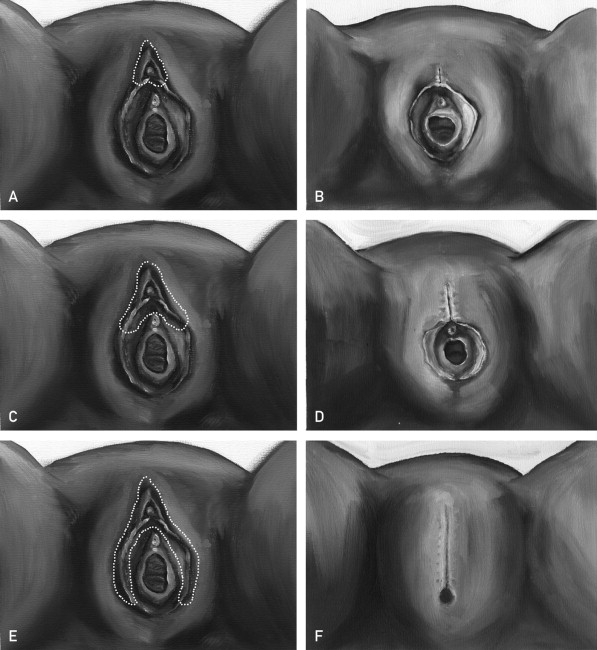

क्या है महिलाओं का खतना यानि FGM:

महिलाओं का खतना यानि FGM (Female genital mutilation) एक ऐसी प्रक्रिया है जिसमें महिलाओं और लड़कियों के योनी के भगोष्ठ को गैर-चिकित्सा कारणों से काटकर निकाल दिया जाता है| इस प्रक्रिया का कोई शारीरिक फायदा महिलाओं को नहीं होता है| इस प्रक्रिया में अत्यधिक रक्तस्राव होता है और इसके बाद महिलाओं में पेशाब की समस्या उत्पन्न हो जाती है. साथ ही कई तरह के संक्रमण और प्रसव के दौरान जटिलताएं भी उभर आती हैं, जिसके कारण कई बार नवजात की मौत भी हो जाती है. जब लड़की छोटी होती है तभी उसके साथ इस तरह की क्रिया को अंजाम दिया जाता है|

महिलाओं का खतना यानि FGM (Female genital mutilation) मे चार से पांच साल की बच्चियों की योनी की भगनासा (Clitoris )और उसके आसपास के भगोष्ठ को छील दिया जाता है| कई बार इस से बच्चियों की मौत भी हो जाती है|

क्या है खतना (FGM) की प्रक्रिया (खतना प्रोसेस इन फीमेल):